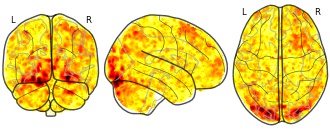

Individual Brain Charting dataset extension, second release of...

- neurovault.org

niftiUpdated Feb 14, 2020 Share

EmailClick to copy linkLink copied Cite(2020). Individual Brain Charting dataset extension, second release of high-resolution fMRI data for cognitive mapping: sub-12_ses-22_task-self_dir-ap_run-03_encode_self [Dataset]. http://identifiers.org/neurovault.image:363181niftiAvailable download formatsUnique identifierhttps://identifiers.org/neurovault.image:363181Dataset updatedFeb 14, 2020License

Cite(2020). Individual Brain Charting dataset extension, second release of high-resolution fMRI data for cognitive mapping: sub-12_ses-22_task-self_dir-ap_run-03_encode_self [Dataset]. http://identifiers.org/neurovault.image:363181niftiAvailable download formatsUnique identifierhttps://identifiers.org/neurovault.image:363181Dataset updatedFeb 14, 2020LicenseCC0 1.0 Universal Public Domain Dedicationhttps://creativecommons.org/publicdomain/zero/1.0/

License information was derived automaticallyDescriptionCollection description

The individual Brain Charting (IBC) Project is using high resolution fMRI to map 13 subjects that undergo a large number of tasks: the HCP tasks, the so-called ARCHI tasks, a specific language task, video watching, low-level visual stimulation etc. The native resolution of the data is 1.5mm isotropic. Their main value lies in the large number of contrasts probed, the level of detail and the high SNR per subject. This dataset is meant to provide the basis of a functional brain atlas. We upload here smoothed individual SPMs. The uploaded maps comprise session-specific and fixed effects across maps acquired with AP and PA phase encoding directions.

Note that Neurovault collection #4438 is a subset of that one. In the present collections, some details have been fixed, including mroe accurate and unique file naming.

Subject species

homo sapiens

Modality

fMRI-BOLD

Analysis level

single-subject

Cognitive paradigm (task)

Self evaluation task

Map type

Z

- N